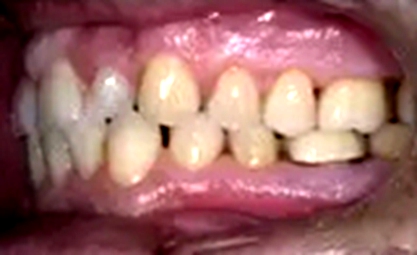

一位尋求改善微笑面容的43歲荷蘭阿爾梅勒男子通過其全科牙醫(yī)的介紹來到一家正畸醫(yī)生的私人診所,以糾正其錯合畸形并在上頜前牙區(qū)域放置6個貼面。他屬于牙形I類錯合畸形,輕度骨性III類,覆合和覆蓋減少以及前牙區(qū)存在間隙(圖1)。

在最初的正畸咨詢期間,拍攝了口內(nèi)和口外照片連同一張全景片(圖2),一張側(cè)位頭影片(圖3)和正畸研究模型的海藻酸鹽印模。